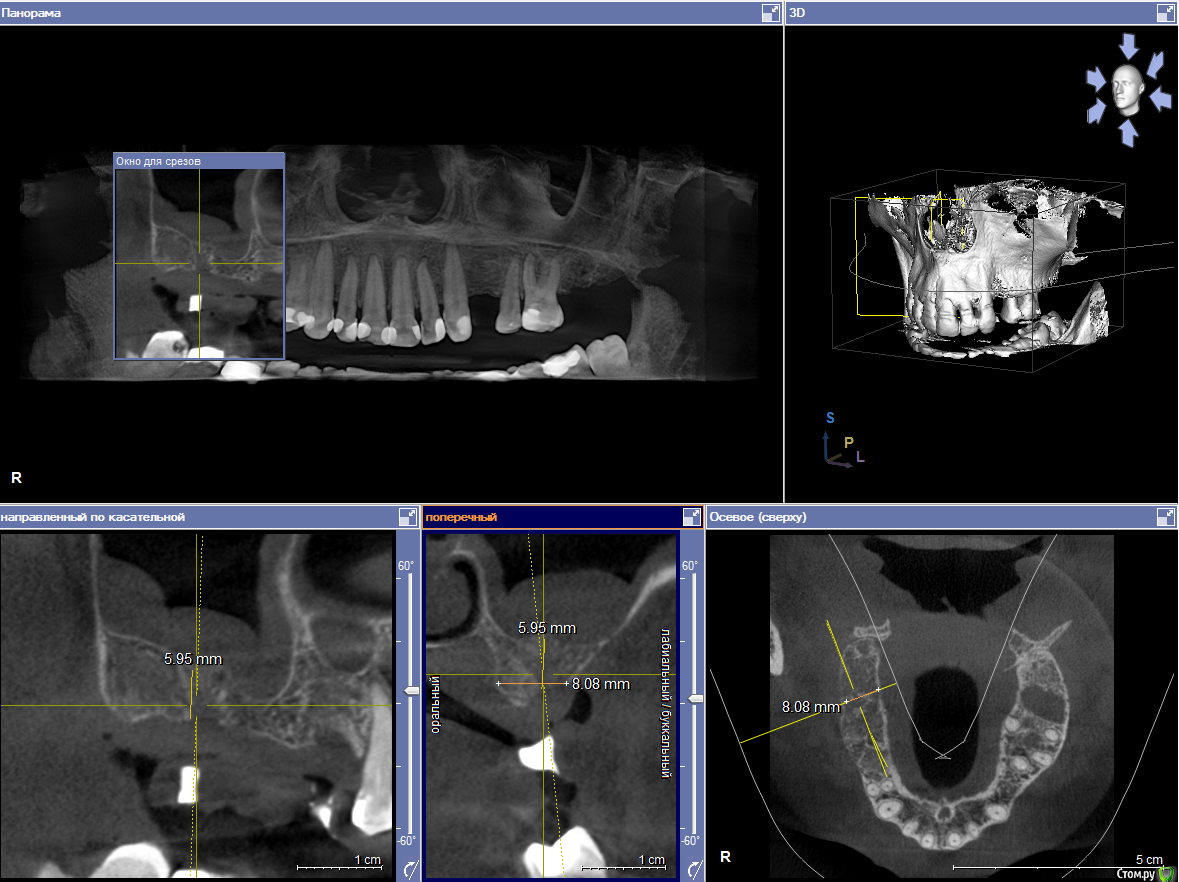

Пациентка пришла с целью восстановления отсутствующих 15,16,17,24,27 з.

Из анамнеза - хронический двухсторонний синусит, соответствующие зубы удалены более 5-ти лет назад, тетрациклиновые зубы ( от изменения цвета отказалась ).

Хирургический план :  консервативное лечение у ЛОР специалистов

1) имплантация в позиции 15,17 з с закрытым синусом и незначительной НКР

2) коррекция слизистой в области 1-го сегм

3) имплантация с ССТ в позиции 24 з ( после дистализации 25,26 з), в области 27 з на момент  операции был гнойный синусит, отложили